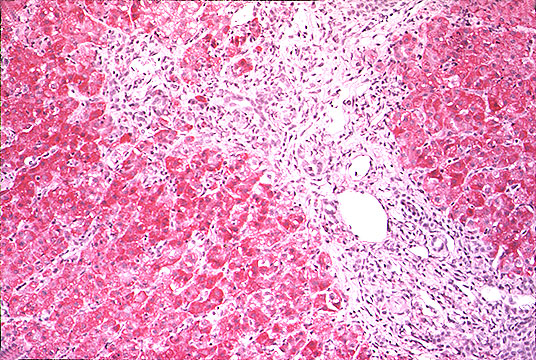

Portal and periportal inflammation

Fig 102 - Portal and periportal inflammation: Portal inflammation is always present in most portal tracts. The inflammatory cell s are mostly lymphocytes sometimes forming lymphoid follicles, plasma cell containing gamma globulins mostly IgG type, macrophages containing iron granules. There may be bile duct damage. Periportal inflammation with disruption of periportal limiting plate and piecemeal necrosis is also present. An acute hepatitis with portal inflammation and many segmented leucocyte and eosinophils is usually not viral. In this case of acute hepatitis B there is marked portal inflammation and periportal piecemeal necrosis with ballooned hepatocyte.